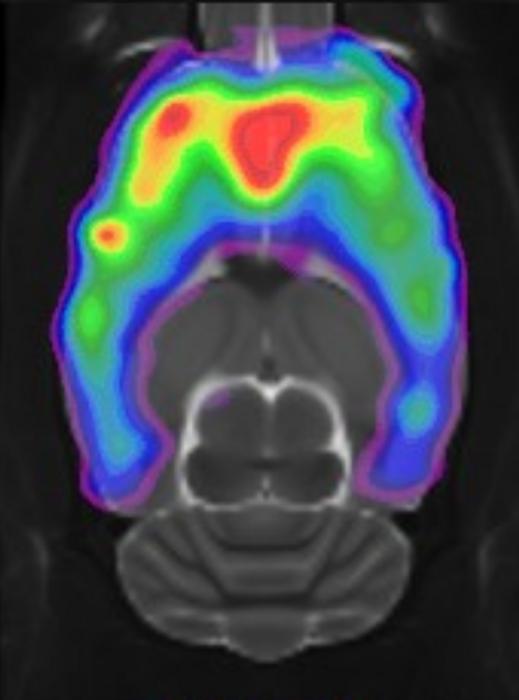

Additionally, an increase in the number of connections to the thalamus region of the brain, which serves as a kind of filter for our decisions and concerns, was observed.

- The change in connectivity to the thalamus may contribute to our enhanced resilience to stress factors and could explain why so many people report positive effects on their well-being from small doses of psychedelic mushrooms.